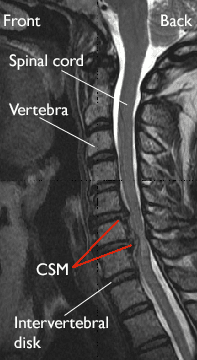

MRI scan of a herniated disk

This magnetic resonance imaging (MRI) scan shows herniated disks pressing on the spinal cord (red arrows), a common cause of CSM.

Reproduced from Boyce R, Wang J: Evaluation of neck pain, radiculopathy and myelopathy: imaging, conservative treatment, and surgical indications. Instructional Course Lectures 52. Rosemont, IL, American Academy of Orthopaedic Surgeons, 2003, pp.489-495.